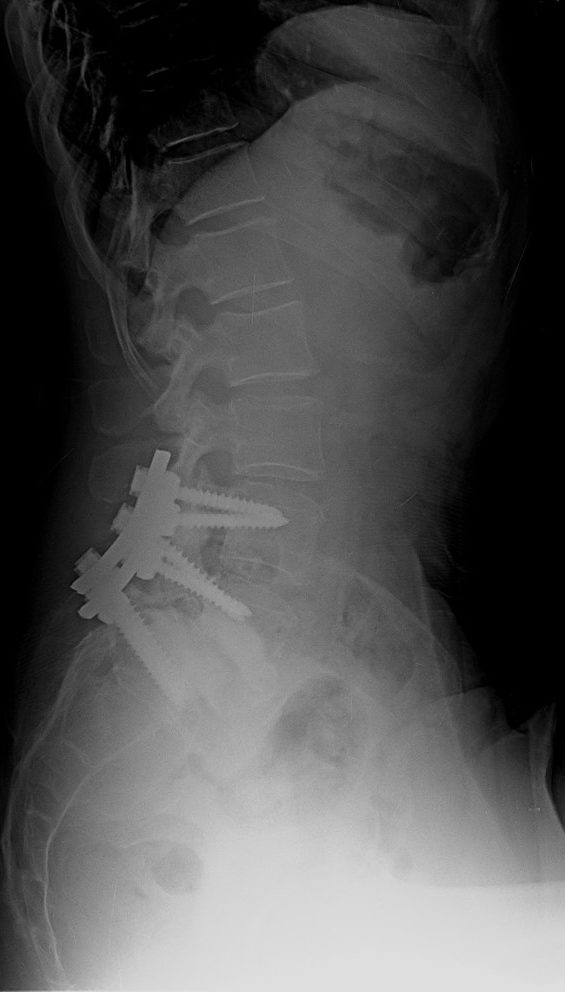

51 Yaşında Kadın Hasta

Bel ve sağ bacak ağrısı

NM normal

Ameliyat Öncesi

Ameliyat Sonrası